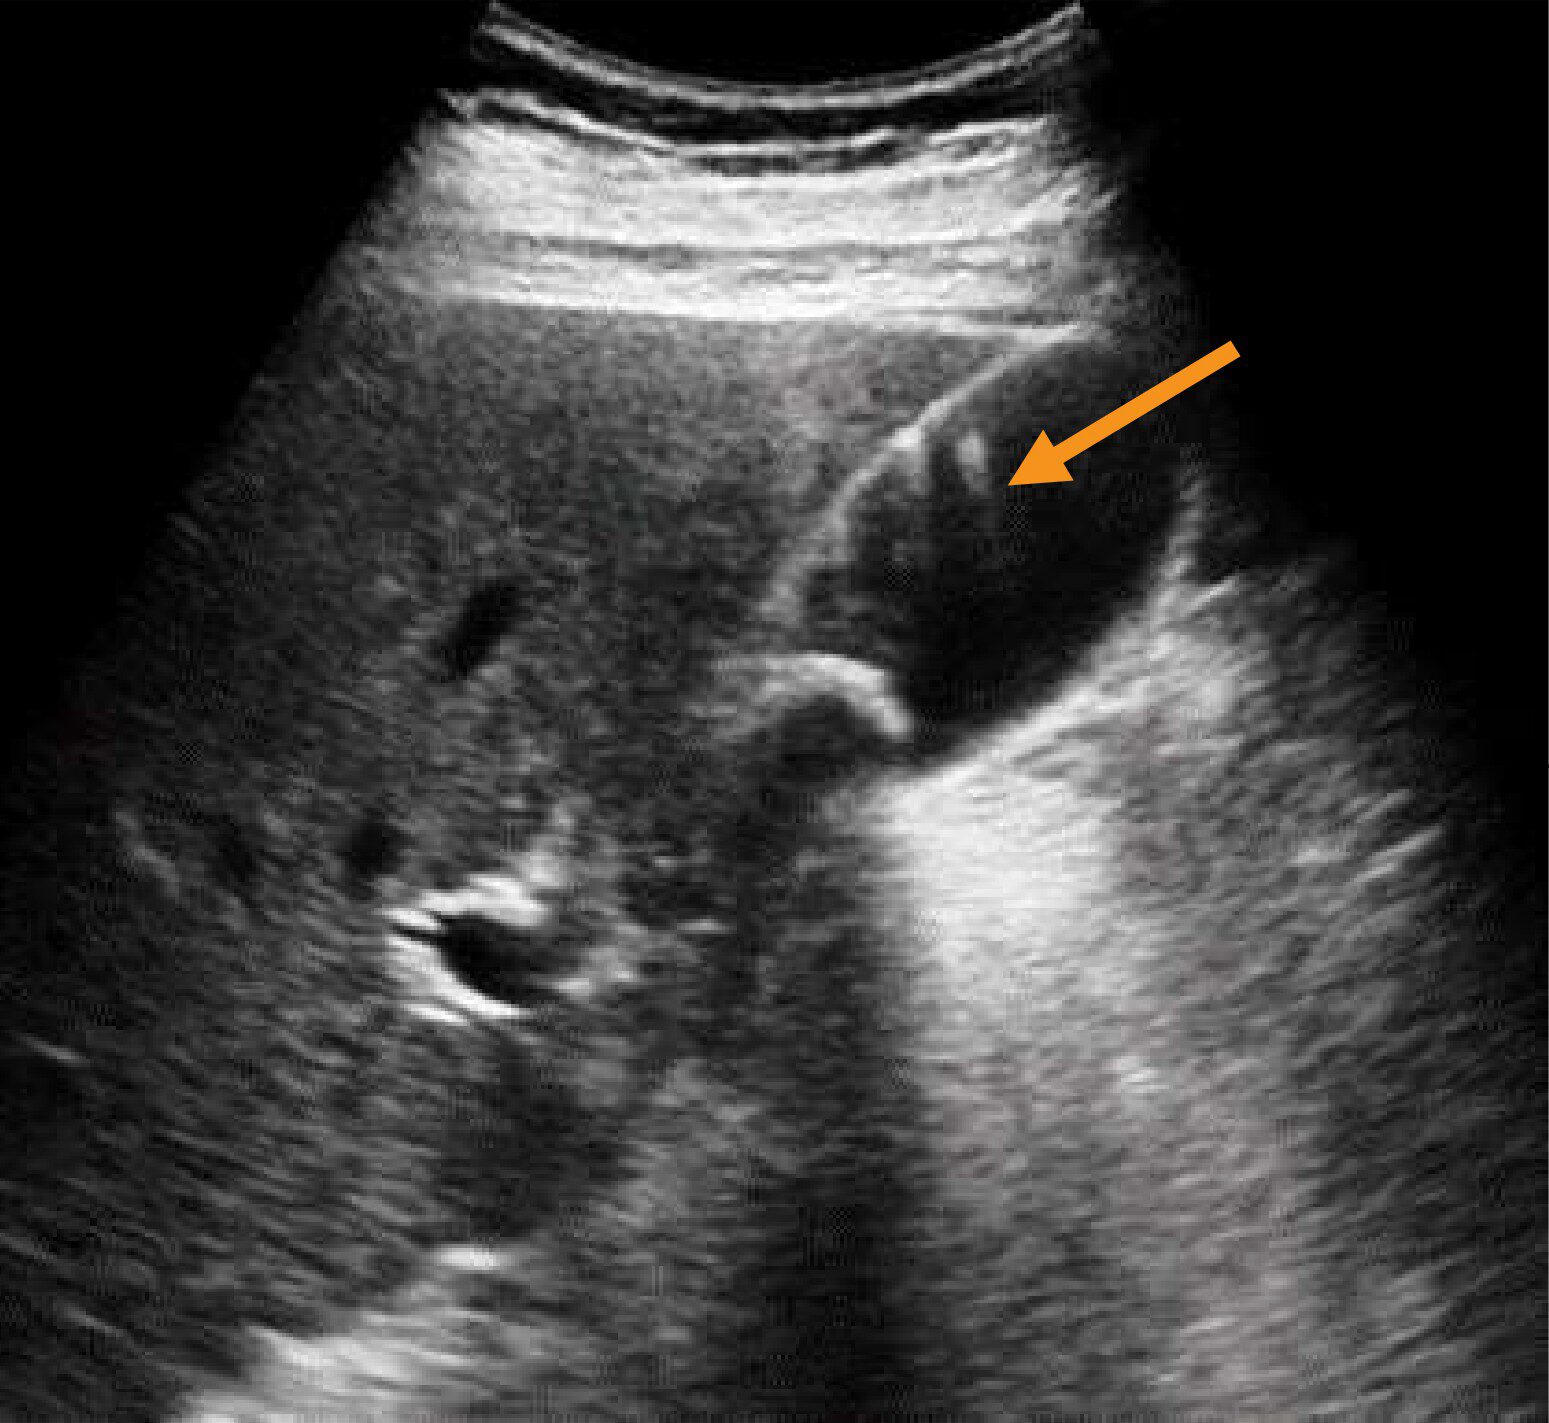

右季肋部縦走査の超音波像(別冊No.2)を別に示す。矢印で示すアーチファクトはどれか。

- 1音響陰影

- 2外側陰影

- 3鏡面反射

- 4側方陰影

- 5多重反射